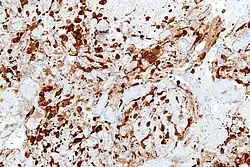

Neuron-specific enolase (NSE) immunostaining of a cerebellar hemangioblastoma.

Detection of NSE with antibodies can be used to identify neuronal cells and cells with neuroendocrine differentiation. NSE is produced by small-cell carcinomas, which are neuroendocrine in origin. NSE is therefore a useful tumor marker for distinguishing small-cell carcinomas from other tumors.[7]